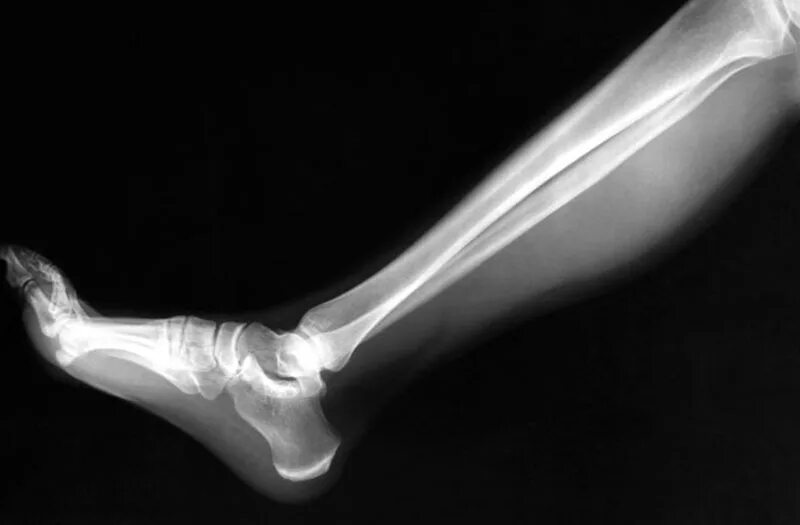

Снимок костей как называется